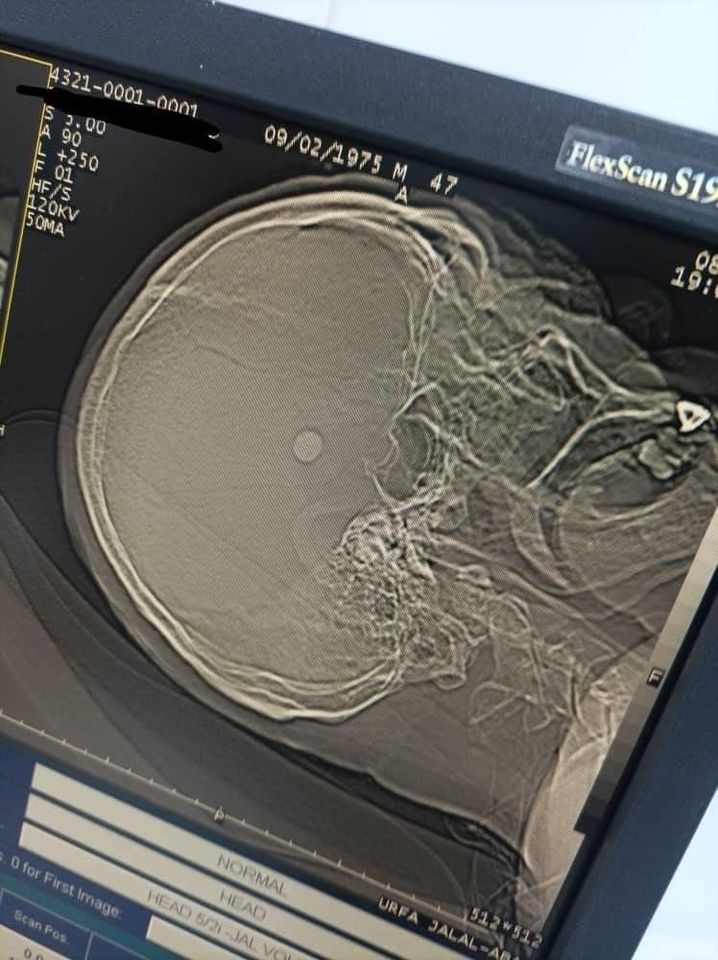

По его данным, пациент поступил с открытым проникающим ранением головы — пуля находилась в лобно-височной доле справа.